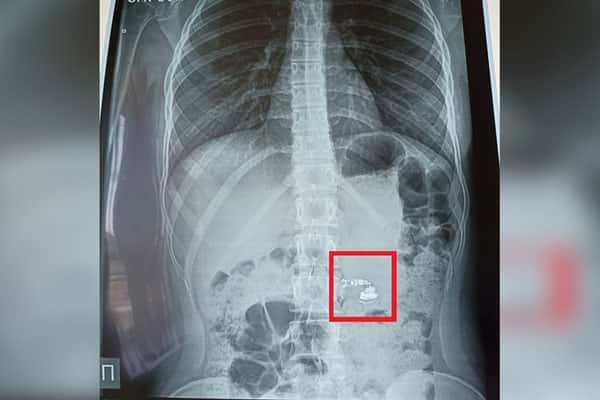

Вечером, как обычно, школьница уснула, не подозревая о том, что произойдет во время ночи. Но проснулась она от резкой боли в горле. Пугаясь и озадаченная отсутствием наушников, она сразу же обратилась за помощью к своим родителям. Быстро вызванная скорая помощь доставила девочку в больницу, где ей сделали рентген. К удивлению всех, наушник обнаружили в кишечнике.

Глава Министерства здравоохранения Башкирии, Айрат Рахматуллин, подчеркнул, что в данном случае обошлось без оперативного вмешательства. Наушник покинул организм девочки естественным путем, не вызывая осложнений. Тем не менее, этот случай является напоминанием о важности принятия мер предосторожности при использовании беспроводных наушников.